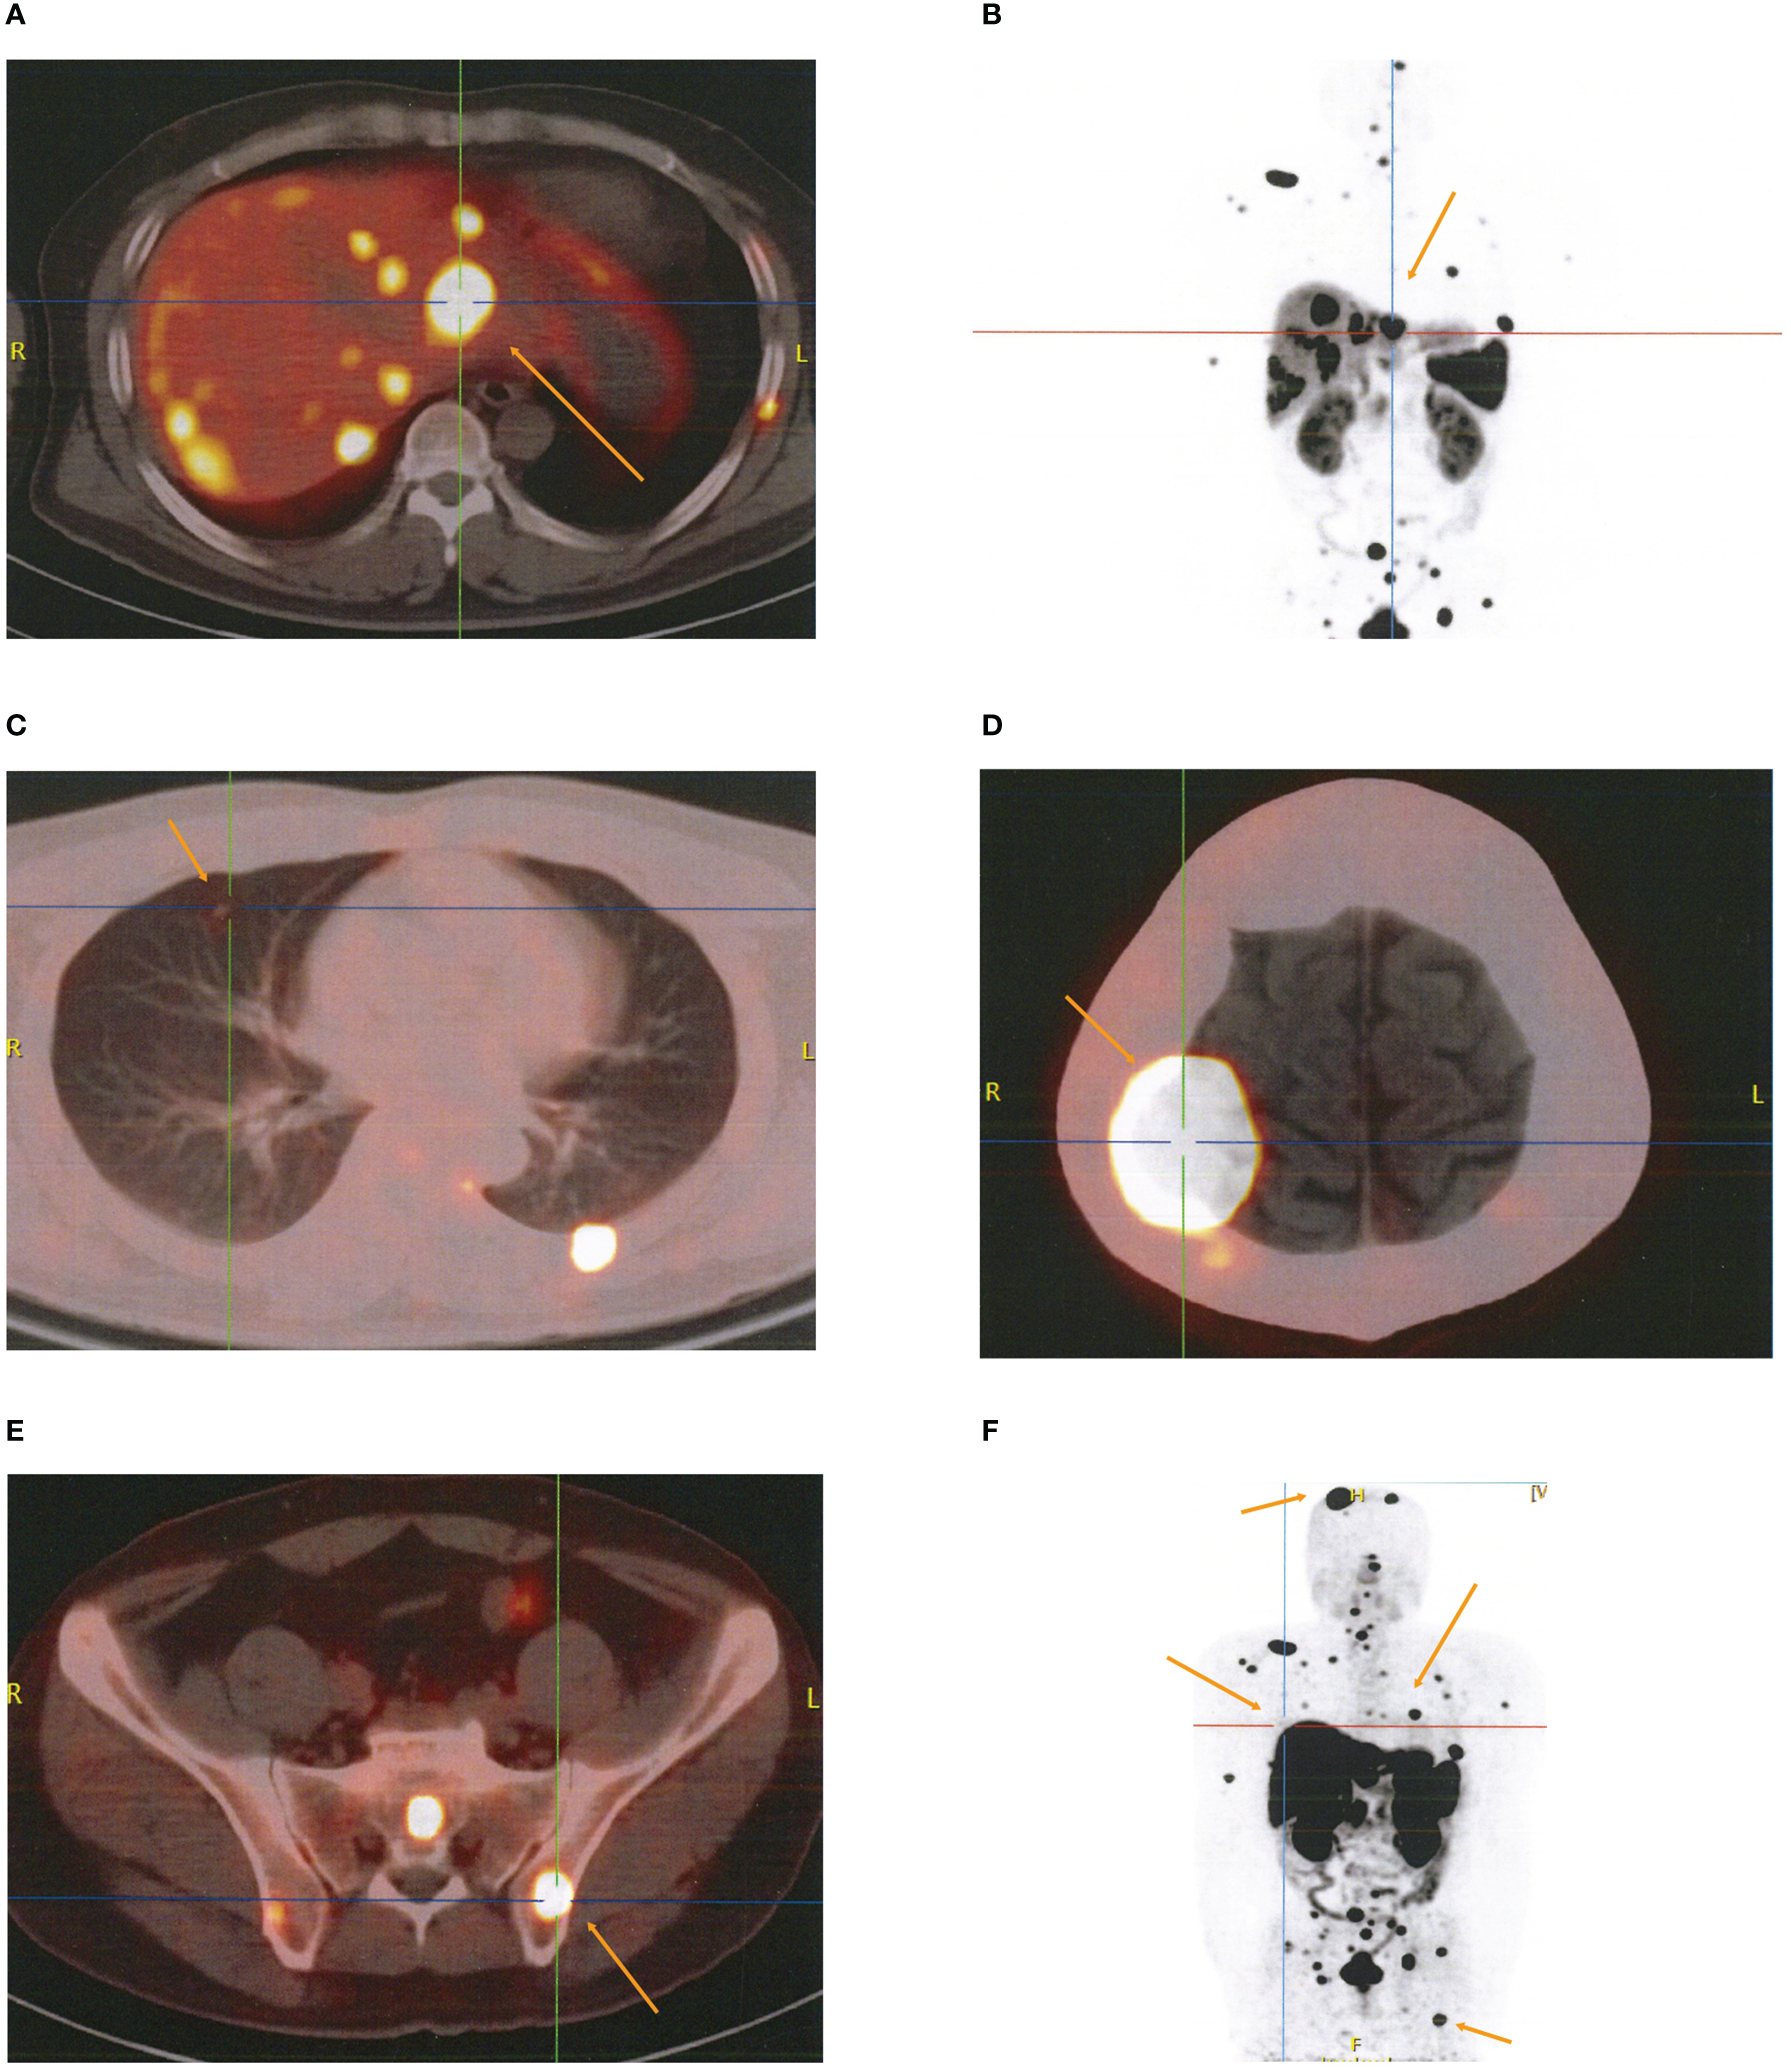

The patient was admitted to the Cancer Center because a skull mass was found on the 8th month after surgery without regular follow-up. The 18F-FDG positron emission tomography (PET)/CT findings indicated multiple high uptake liver (2.8 cm × 2.4 cm) with a maximal standardized uptake value (SUVmax) of 17.7 and bilateral pulmonary nodules with a maximum diameter of 0.5 cm (Supplementary Figures 3A–C), as well as high uptake masses and osteolytic bone destruction in the right parietal skull bone, vertebral body, and ilium (Supplementary Figures 3D, E). These results revealed that the metastatic localizations of bladder PGLs were in the liver, lung, and bones. The patient underwent 18F-DOTATATE PET/CT targeted imaging as a result of the positive expression of SSTR2. The results showed multiple high uptakes of liver and lung nodules with a SUVmax of 65.0 and 2.2, respectively (Figures 3A–C), as well as a high uptake mass with osteolytic bone destruction of the right parietal skull and iliac bone (Figures 3D–F). These results of 18F-DOTATATE PET/CT confirmed the same diagnosis. The level of vanillylmandelic acid (VMA) in 24-h urine was 24.80 mg/24 h (normal range ≤12.00 mg/24 h) (Figure 4Q).

Figure 3

The results of 18F-DOTATATE PET/CT for metastatic localizations of paragangliomas. (A–C) Multiple high uptake localizations in liver (A, B) and lung (C). (D, E) High uptake localizations with osteolytic bone destruction of right parietal skull bone (D) and ilium (E). (F) Whole-body SPECT/CT imaging.